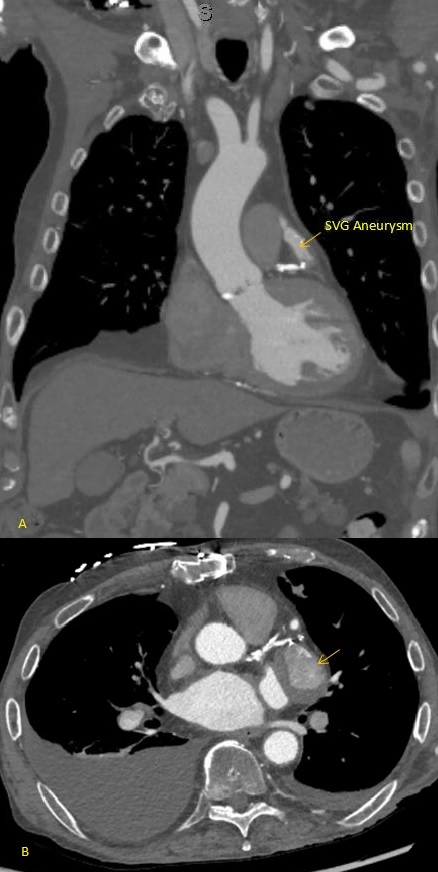

An 80-year-old patient with a history of coronary artery disease status post CABG in 2021, paroxysmal atrial fibrillation, heart failure with preserved ejection fraction, severe mitral regurgitation status post TEER-MitraClip, and moderate-to-severe aortic stenosis (aortic valve area 0.6 cm2, mean gradient 31 mmHg) presented with progressive exertional dyspnea, weakness, and lightheadedness. Transthoracic echocardiography confirmed moderate-to-severe aortic stenosis, and a cardiac CT was obtained for transcatheter aortic valve replacement (TAVR) evaluation. Imaging incidentally revealed a 3.1 cm SVG aneurysm with suspected intraluminal thrombus, prompting initiation of anticoagulation and left heart catheterization to further characterize the aneurysm.

SVG aneurysms are rare and pose a complex clinical challenge. A recent review offers proposed management strategies. Current management requires individualized treatment decisions based on patient risk, aneurysm type, size, presence of complications, whether symptomatic, and available expertise. The three current mainstays of treatment include observation and medical therapy, surgery and percutaneous intervention. Medical therapy and observation are preferred for patients that are high risk surgical candidates, or have multiple comorbidities. Percutaneous interventions are minimally invasive and include covered stents, coils, delivering endoluminal grafts and thrombin injections. Surgery is preferred for those that are hemodynamically unstable, and have acute significant complications. In our case, the patient met criteria and could be managed non-operatively.